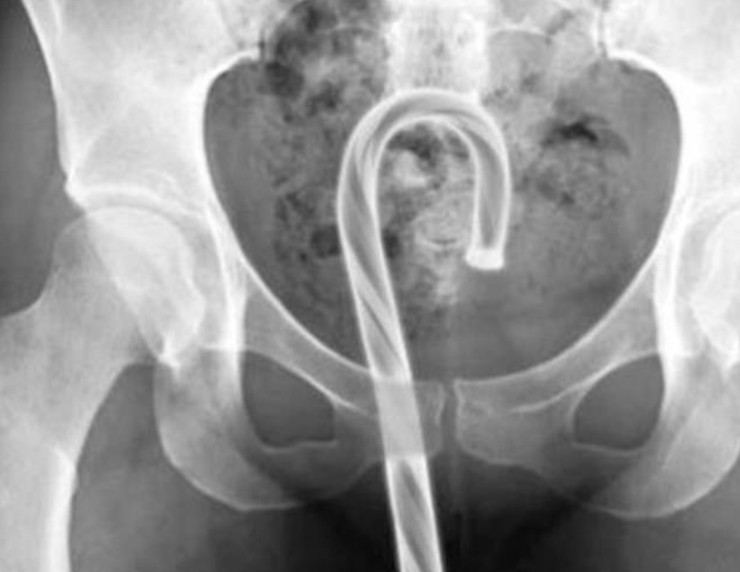

Դանակ, պատառաքաղ, մանկական խաղալիքներ ու գարեջրի շշեր: Այս ամենն ինչ-որ ձևով կարող է հայտնվել օրգանիզմում: Այս նկարները նայելիս կարող եք համոզվել, որ այս կյանքում ամեն ինչ հնարավոր է: